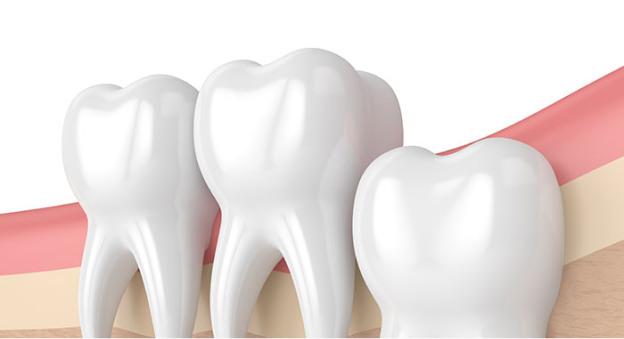

• 사랑니 발치 이유 2

치아가 매복된 경우

사랑니의 일부를 잇몸이 덮고 있는 경우 사랑니 주변 잇몸에 염증이 생기기 쉬우며 염증이 심해지면 잇몸과 볼에도 부종이 생길 수 있습니다.